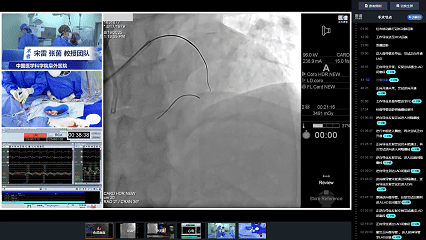

全景手术复盘

手术过程

结合全景手术复盘,张茵教授详细阐述CTO PCI操作技巧与策略思考: